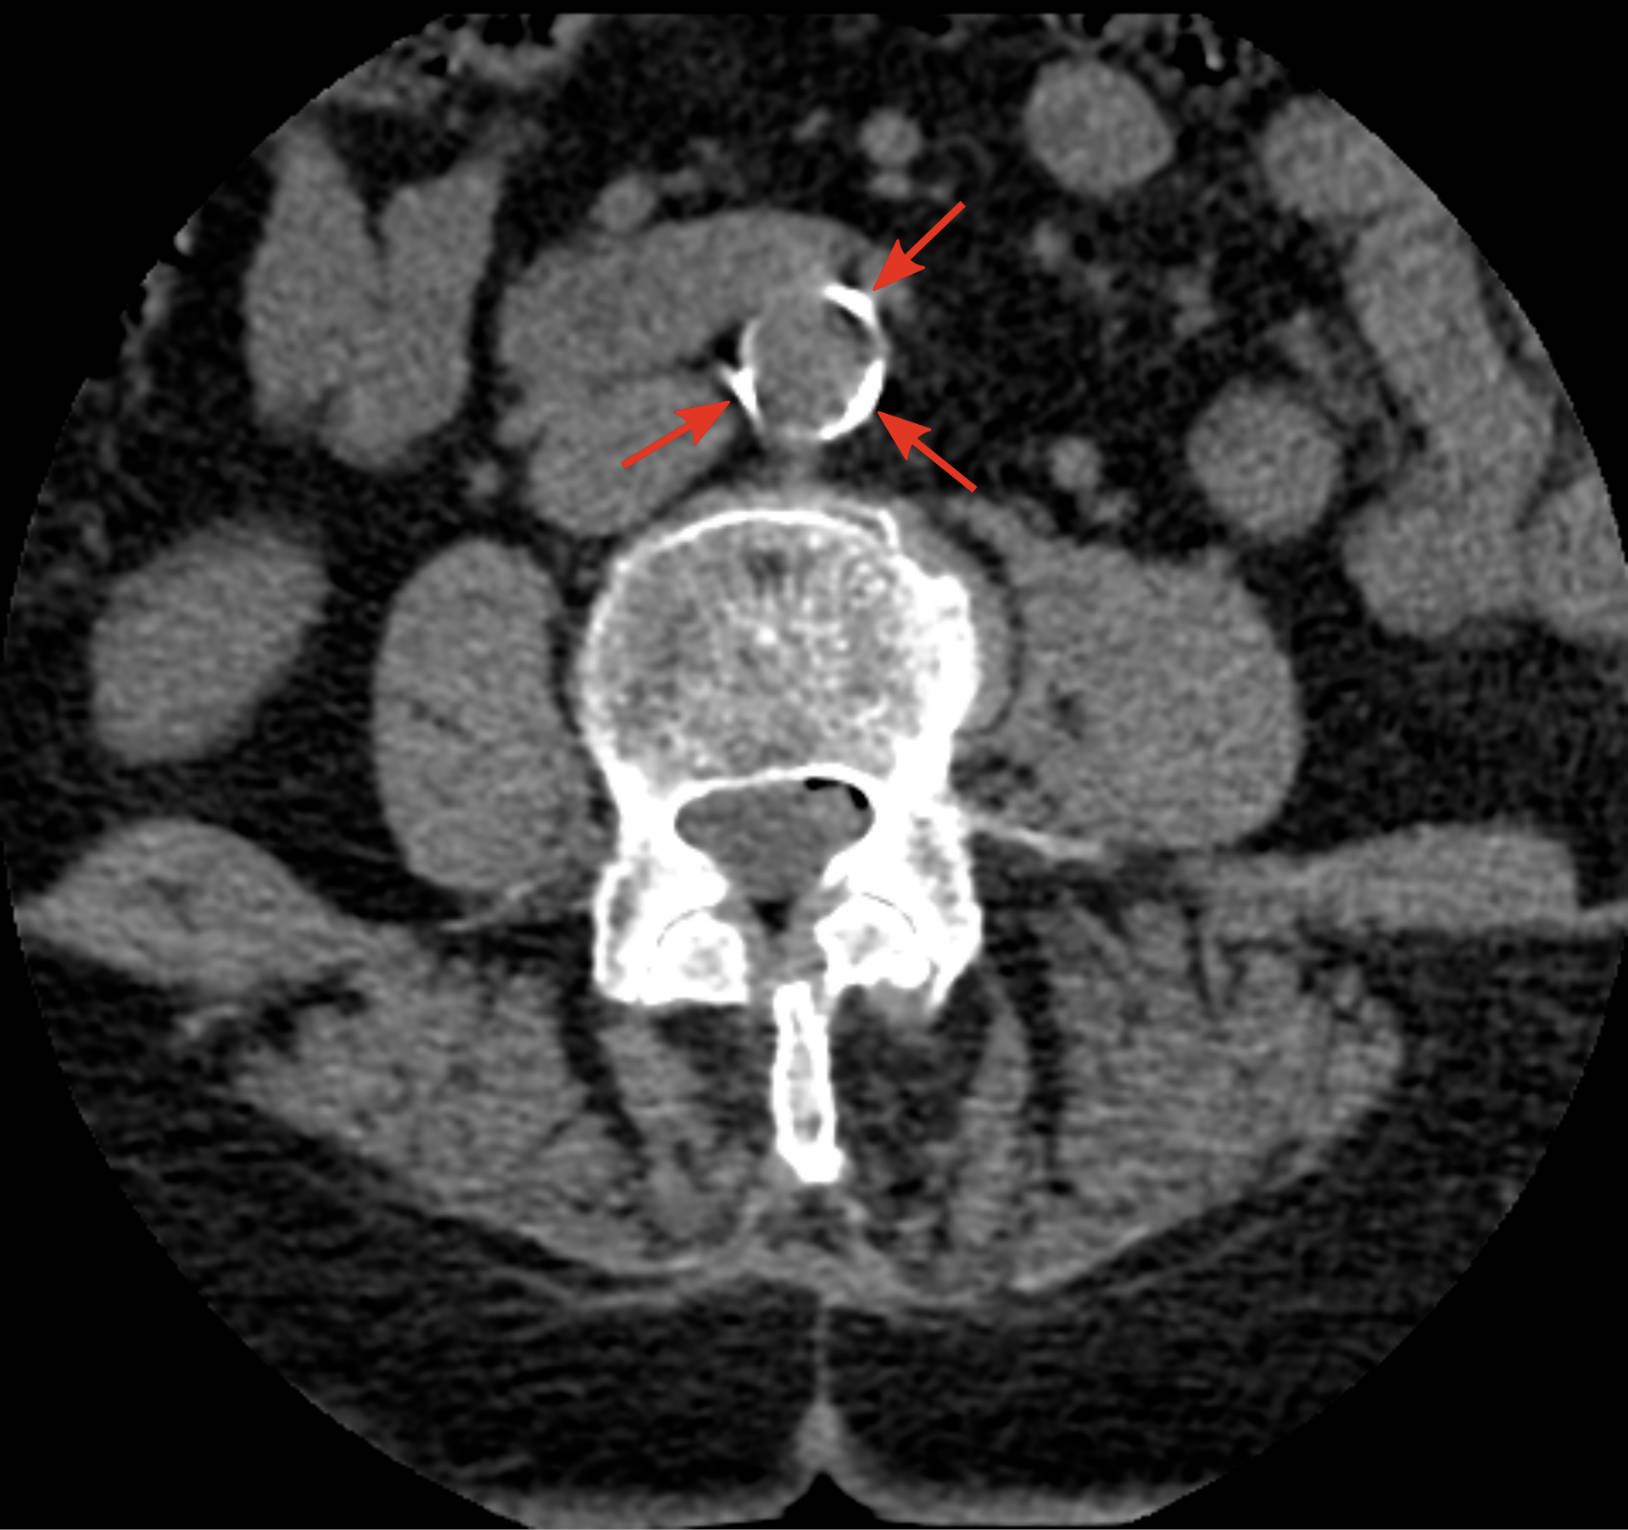

This computed tomography (CT) image provides a detailed view of atherosclerosis affecting the abdominal aorta in a 70-year-old woman with a history of hypertension and dyslipidemia. We will explore the key features highlighted in this scan, discuss the underlying medical condition, and provide comprehensive insights into its implications for patient health. This analysis aims to enhance understanding of a common cardiovascular concern in an aging population.

Arrows: These arrows point to significant calcifications within the wall of the abdominal aorta, indicative of advanced atherosclerosis. These calcified plaques narrow the arterial lumen and reduce the elasticity of the vessel, impeding normal blood flow. Such findings are critical in assessing cardiovascular risk and guiding treatment strategies.

The presence of calcified plaques, as visible in the CT scan, signifies a long-standing atherosclerotic process. These calcifications are not merely inert deposits but rather markers of ongoing vascular damage. The stiffening of the aorta due to these plaques increases the workload on the heart and can lead to various complications.

Over time, these fatty streaks progress into fibrous plaques. Smooth muscle cells migrate from the media (middle layer) of the artery to the intima (inner layer) and proliferate, laying down collagen and forming a fibrous cap over the lipid core. Calcium also begins to deposit within these plaques, leading to the calcifications observed in the provided CT image. These calcified plaques harden the arterial walls, reducing their elasticity and narrowing the lumen. The compromised blood flow can lead to a range of symptoms, from mild discomfort to severe, life-threatening events. The aorta, being a major conduit for blood distribution, is particularly vulnerable to the systemic effects of this disease.

Understanding the intricacies of abdominal aortic atherosclerosis, especially in individuals with established risk factors like hypertension and dyslipidemia, is paramount for both clinicians and patients. The CT image serves as a powerful diagnostic tool, visually confirming the presence and extent of calcified plaques. By integrating detailed imaging findings with comprehensive patient history, healthcare providers can formulate tailored management plans aimed at mitigating disease progression, preventing severe complications, and ultimately enhancing the patient’s quality of life. Proactive screening and diligent management of cardiovascular risk factors remain the cornerstone of addressing this prevalent condition.